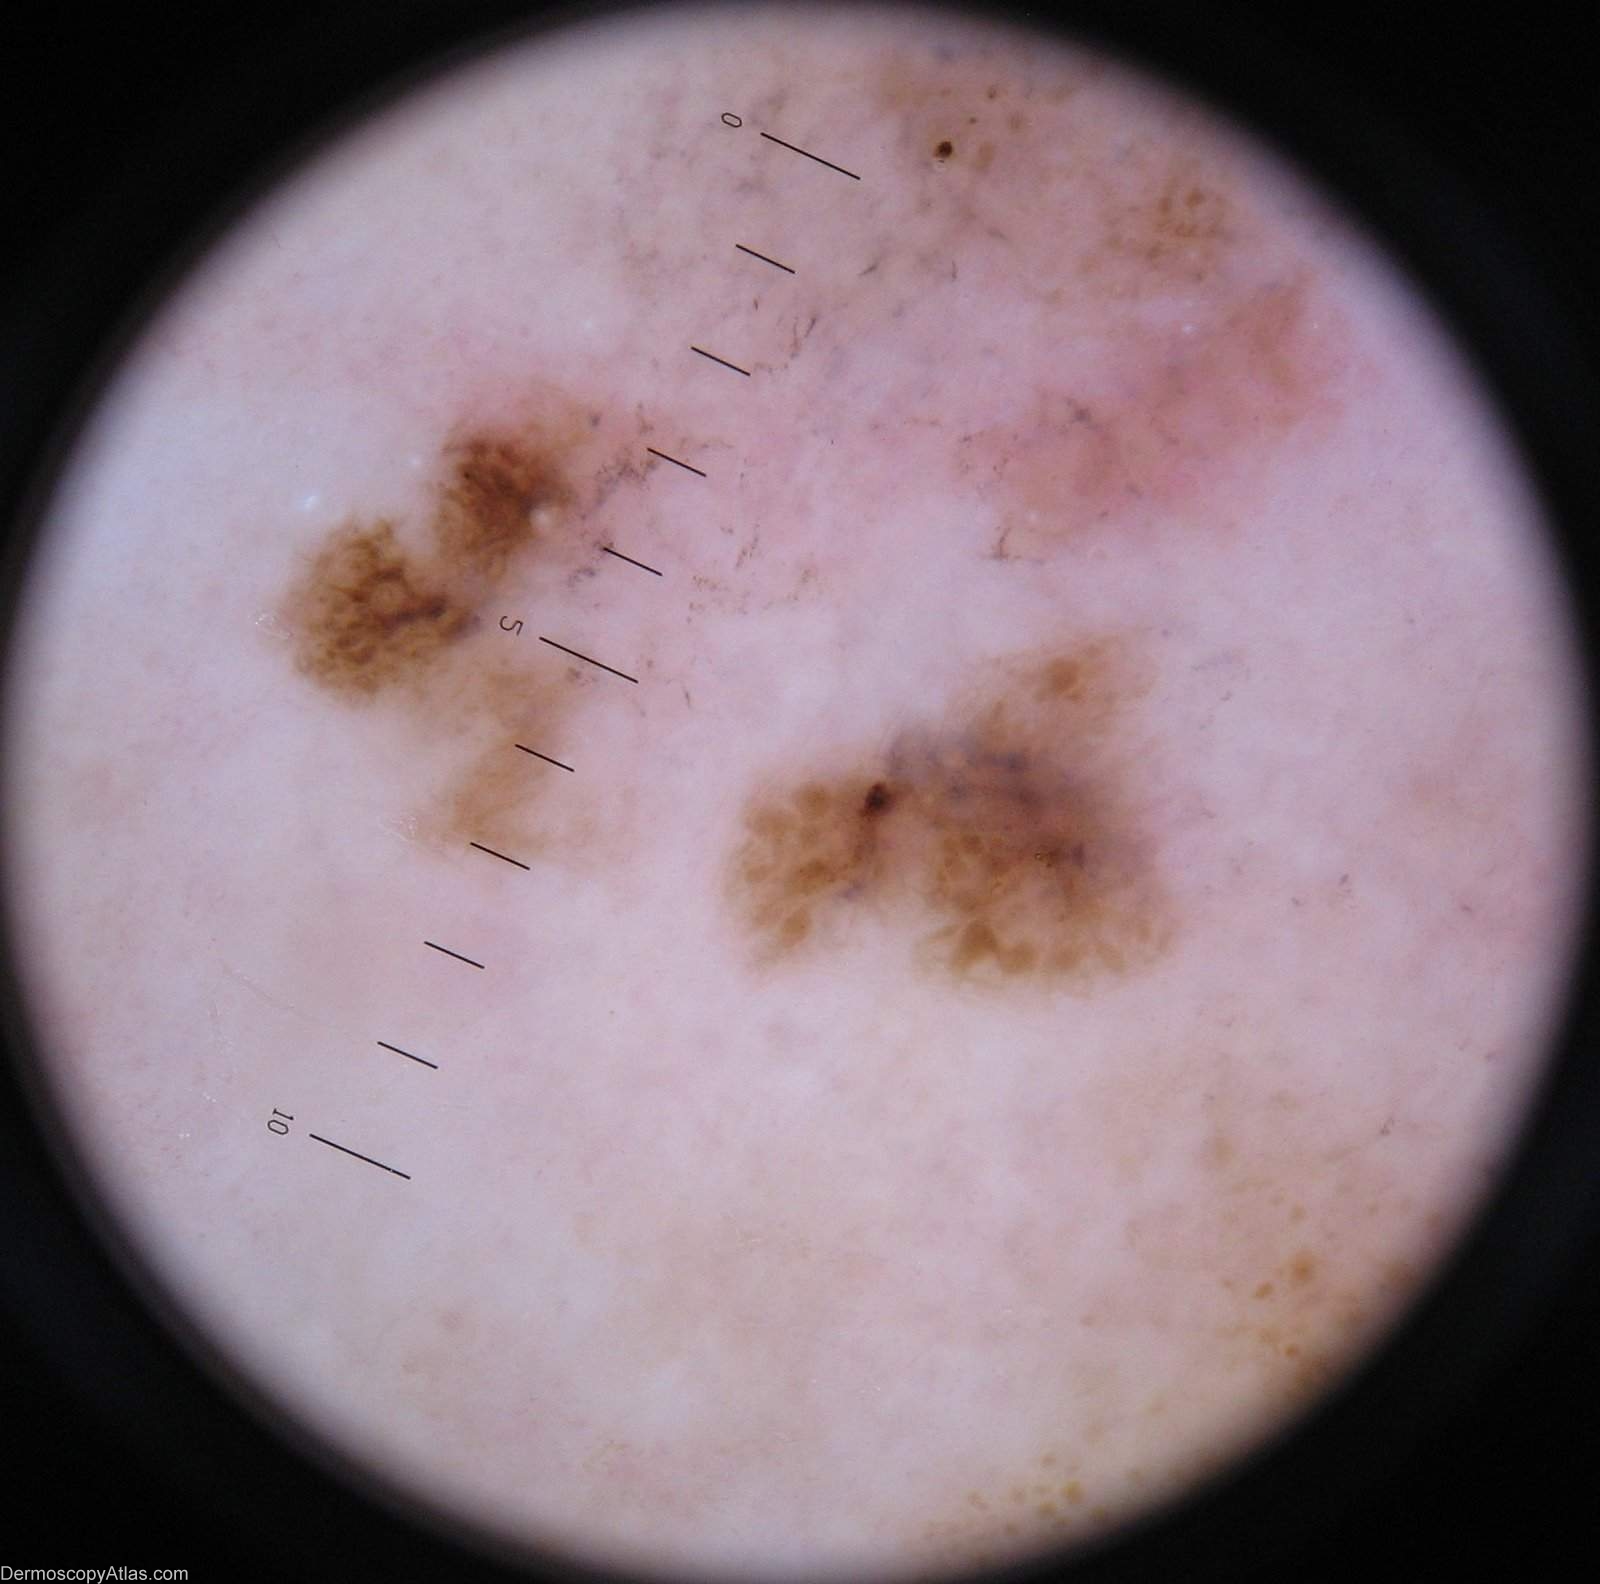

Diagnosis: Melanoma regression

Description: Lesion on the calf. Clinically areas of regression are shown in both the pale and grey areas

Case courtesy of Dr Greg Canning This poorly demarcated lesion is approx 5 cm in diameter and has resided on the left proximal postero medial calf of it's 72 year old owner for as long as she can remember. On reflection however she thinks it may have enlarged somewhat over the years. She has been repeatedly reassured about it by the doctors who have treated her numerous non melanoma skincancers.

Histopathology of incisional biopsy There is an atypical melanocytic lesion composed of disparate foci separated by zones of regression. There are moderately to markedly atypical melanocytes forming irregular junctional nests and invading the epidermis. A lichenoid dermal inflammatory infiltrate is present and there are two foci of superficial nvasion of the dermis to the interface of papillary and reticular dermis. The Breslow thickness in each case is 0.4 mm. Mitoses are rare. The minimum clearance of the invasive components is 2.5 mm from the 3 o'clock margin. Atypical junctional nests almost abut the 3 o'clock edge.

The degree of regression obfuscates interpretation of the precursor lesion, but lentiginous activity is seen and involvement of a hair follicle. In combination with the multifocal nature of the lesion it

is likely that this is lentigo maligna melanoma.